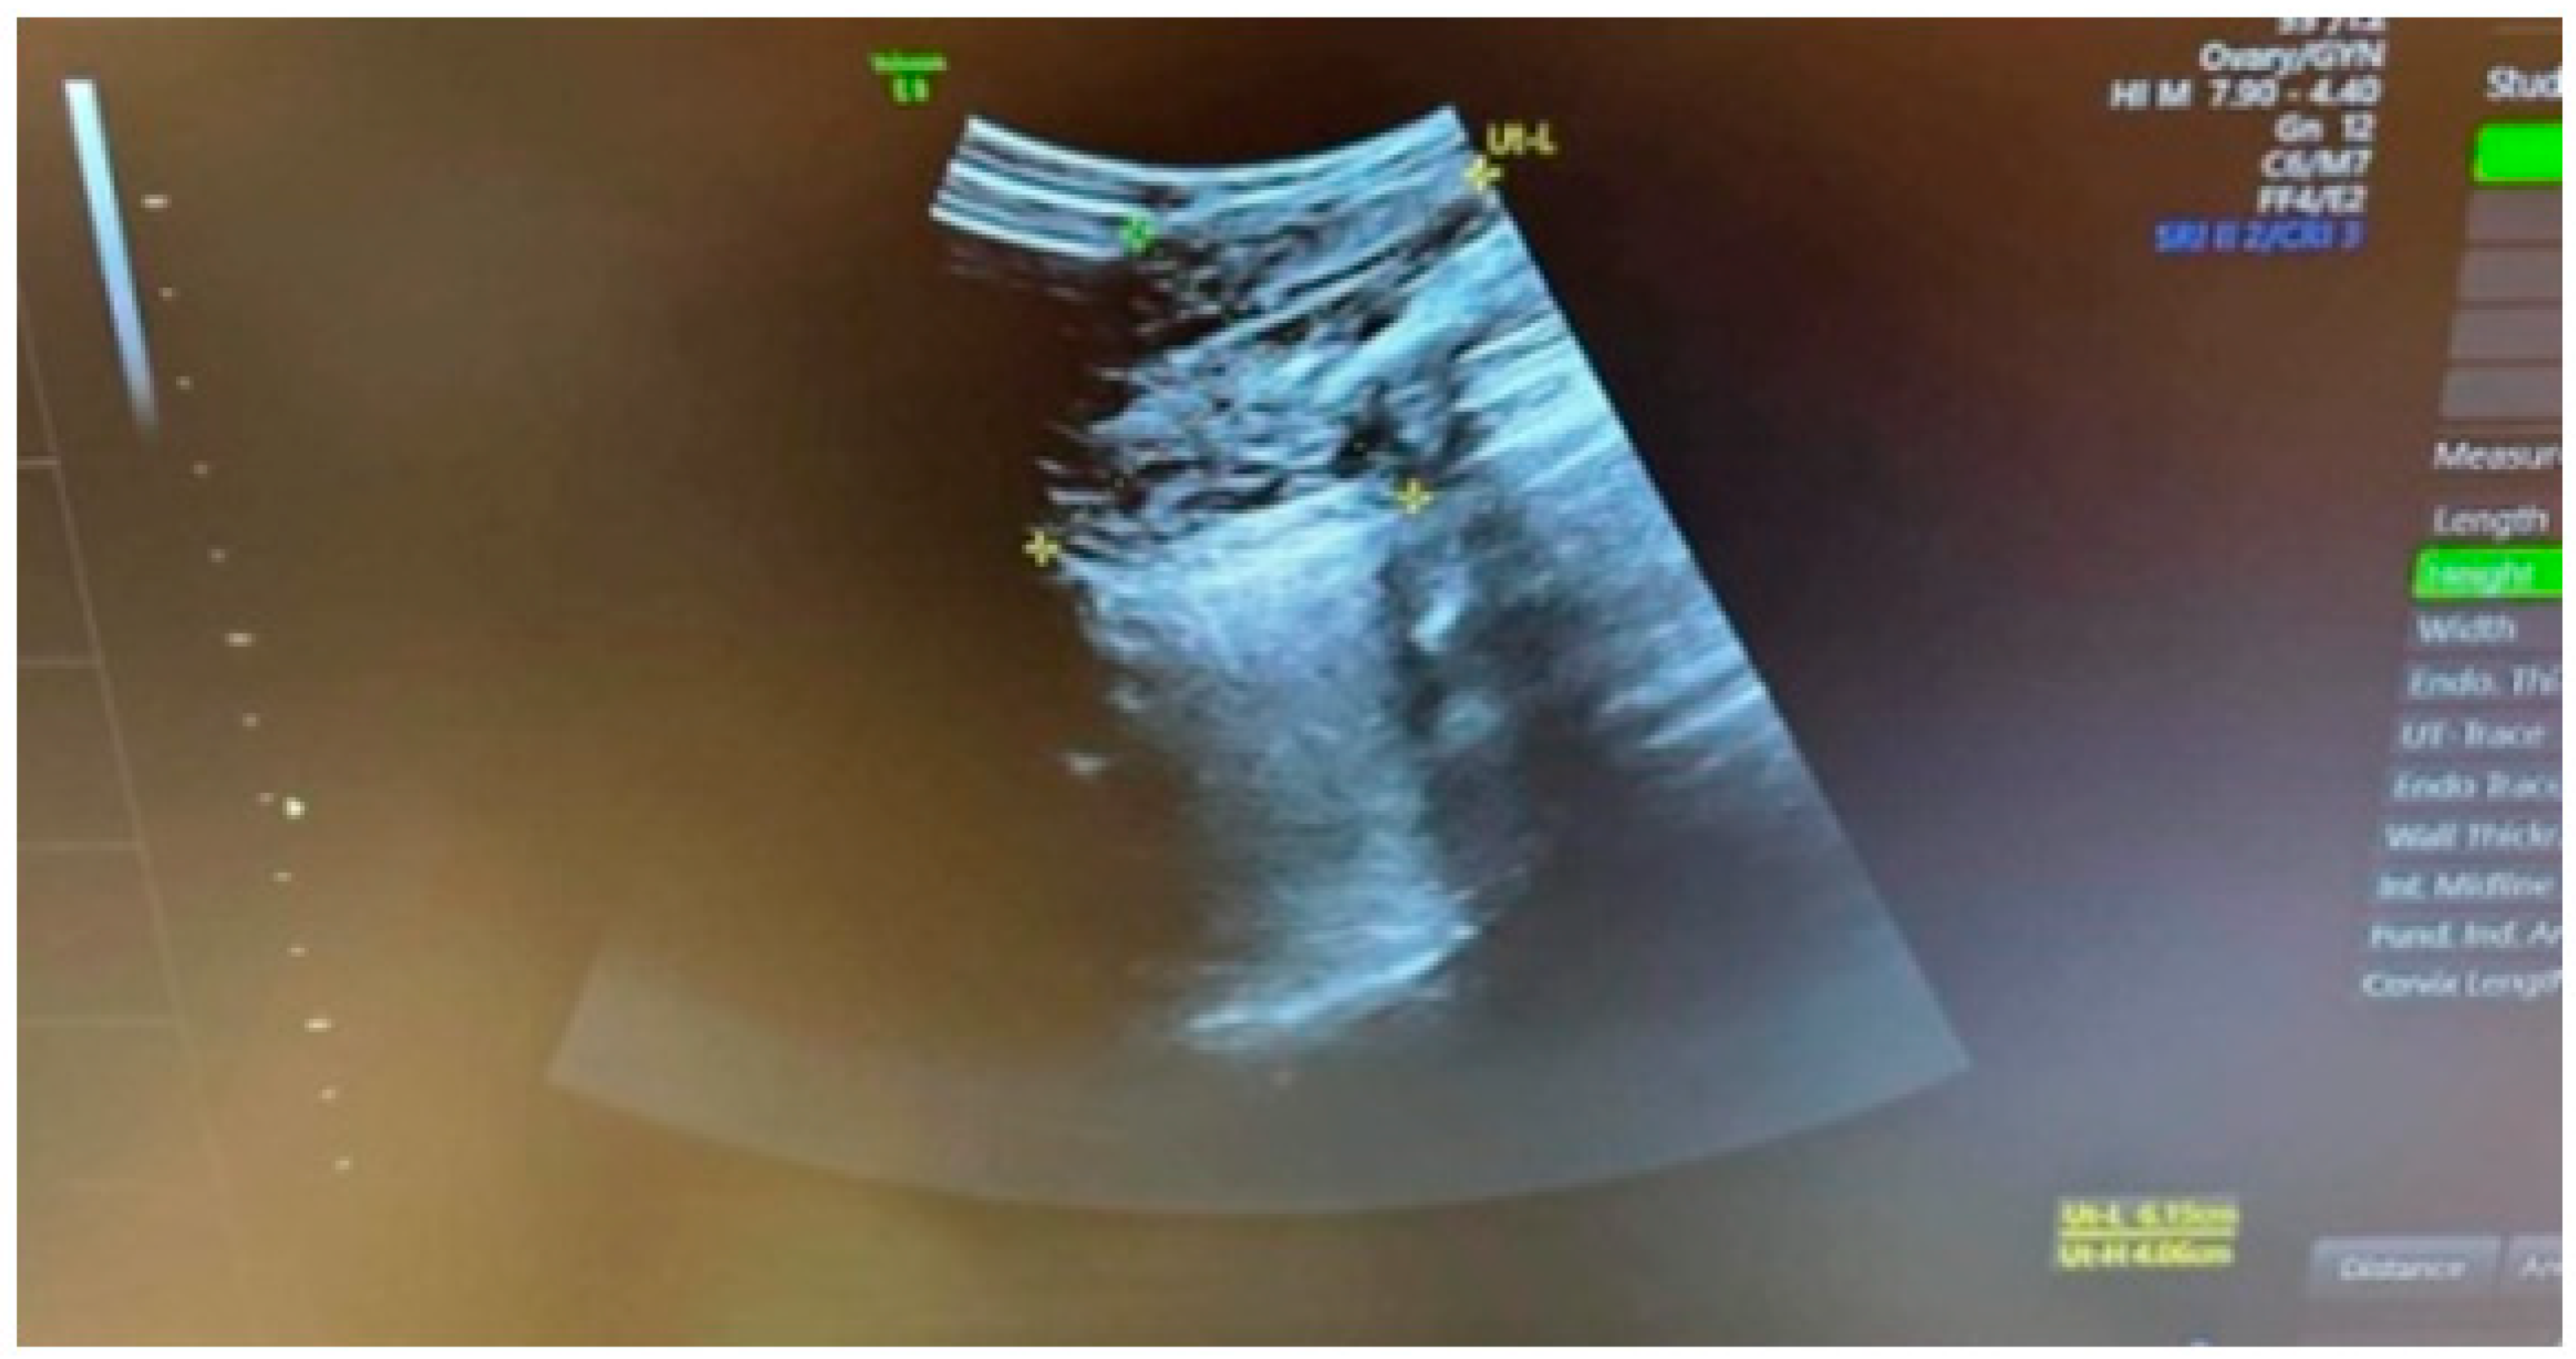

We present a clinical case of an aggressive angiomyxoma located in the left greater labial area in a 50-year-old woman, initially diagnosed as a left inguinal hernia. The patient was referred to a surgeon with a suspected left inguinal hernia. The surgeon rejected the diagnosis and the woman was referred for a consultation with a gynecologist. The history revealed the following information: the patient was 50 years old and had no family history. She reported two children born by caesarean section in 1995 and 2003 and regular menstrual cycles. She denies any concomitant illnesses. According to the patient, an attempted extirpation of a left Bartholin’s gland cyst was performed 12 years ago, but the results were not followed up and medical records were lacking. Gynecologic examination revealed the following: an External genitalia of non-parturition, with a spherical, lobulated, mobile tumor, elastic consistency, located in the left greater labial area, measuring approximately 6/4 cm, without fluctuation. Vagina - compressed by the described formation; PVCU - conical, pink; OECC - round; canalis cervicalis - closed; Ex utero - nihil; Uterus - in AVF, slightly enlarged overall on account of one intramural myoma node located in the area of the anterior uterine wall, 2 cm in diameter. Adnexa and parameters - bilateral normal. Cavum Douglassi - free. Ultrasonography of small pelvis and the described tumor formation was performed: Uterus - in AVF, with increased size on account of one intramural myoma node located in the area of anterior uterine wall with dimensions 20x18 mm; Endometrium - 7 mm thick; Adnexa - accessible, with normal shape and size; Cavum Douglassi - no freely mobile fluid. A superficial, spherical, lobulated and mobile tumor formation, with indistinct borders, with echo heterogeneous contents and measuring 62x40 mm was visualized in the left greater labial area. In Figure 1, we have demonstrated the sonographic image of the described formation (Figure 1). After discussion and informed consent signed by the patient, antibiotic and anticoagulant prophylaxis was administered. On the 27th of January 2023 at the University Hospital “St. Marina” Pleven, under epidural anaesthesia, extirpation of the tumour formation was performed. The stages of the operation are presented in Figure 2, Figure 3 and Figure 4 (Figure 2, Figure 3 and Figure 4).

Figure 1. Sonographic image of the tumor formation.